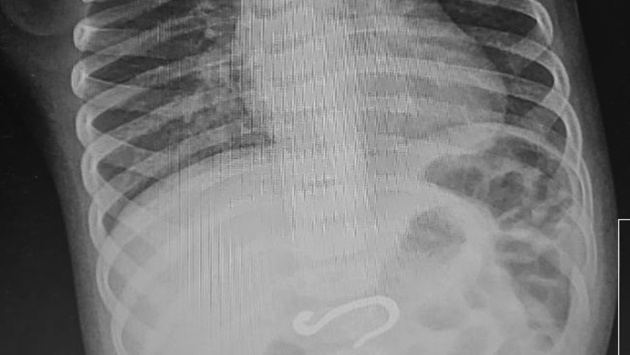

Родители доставили ребенка в экстренный приемный покой ЧОДКБ, заподозрив, что он проглотил колпачок от ручки. Однако рентген показал, что внутри кишечника находится металлический крючок. Сначала врачи решили, что рыболовный, но его форма и толщина поставили их в тупик. Родители тоже не смогли пролить свет на то, откуда мог появиться опасный предмет. Его нужно было достать так, чтобы не поранить внутренние органы.

"Ребенок маленький, объем желудка маленький. Мне этот крюк надо было сначала переместить из кишки в более просторное место желудка, а потом подцепить и аккуратно, не повредив ткани, извлечь наружу. Нам удалось избежать перехода на интубационный наркоз, смогли обойтись масочным, но процедура заняла не менее часа", - рассказала заведующая эндоскопическим отделением Татьяна Лещева.

По словам врача, поменять позицию достаточно инородного тела оказалось непросто. Крючок толщиной с монету несколько раз срывался на уровне пищевода и его приходилось снова ловить и поворачивать так, чтобы он пошел по оси, не повредив ткани.